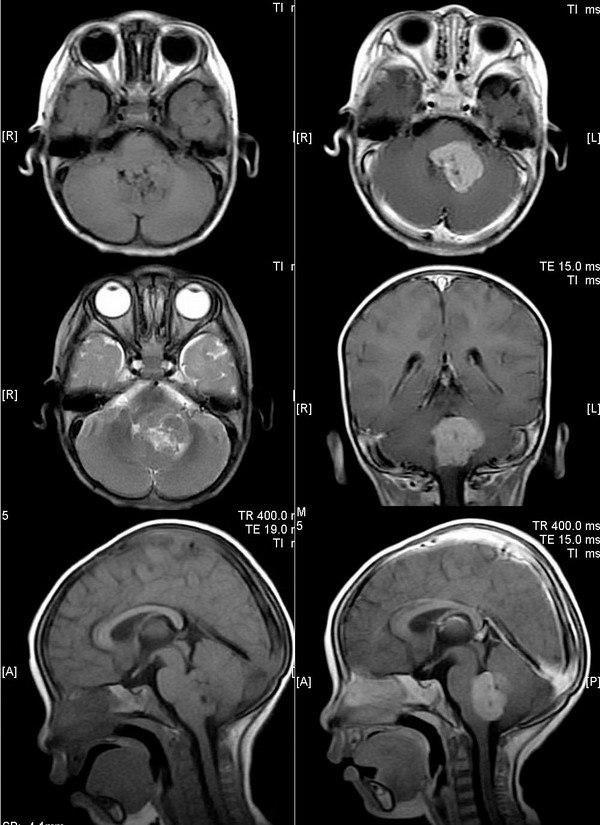

m 3y,头痛,走路不稳半月。

四脑室内占位,t1像呈等、低信号,t2像呈等、高混杂信号,增强病灶明显强化,中间似有低信号点状钙化区,病灶外形欠规则,幕上脑室扩张不明显,首先考虑室管膜瘤,与髓母细胞瘤鉴别。

后颅窝中线占位,t1像呈等信号,t2像呈混杂信号,中等为主,内见散在小片状长t1长t2囊变坏死区,右前方及左后方见新月形脑脊液信号,增强病灶中等强化,病灶外形欠规则,幕上脑室扩张,中脑导水管位置及四叠体板形态未见异常,首先考虑四脑室内占位,室管膜瘤可能性大。

主要是定位:1 如果肿块后方见脑脊液信号,说明是四室内的;;如果后方未见仅前方见脑脊液信号,说明是小脑的。2 中脑导水管位置是否前移,四叠体板形态是否上移,移位者为髓母。3 乳头状瘤t1多呈低信号,明显不支持。

ped0639病理结果为:髓母细胞瘤